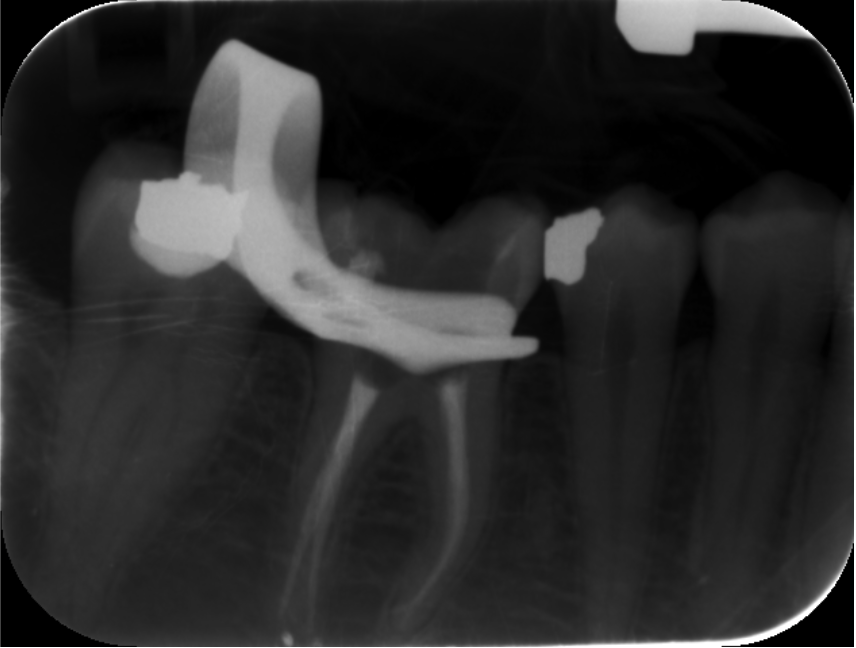

These included team building, communication, photography, endodontics, composite and amalgam restorations, oral surgery, prosthodontics and paediatric dentistry Through these courses I was able to improve on my knowledge and skills from university and implement them in my everyday practice. I have also been keeping a photographic record of my work throughout this year which allows me to reflect on what went well and what I can improve on in the future. space to display your timeline of professional development